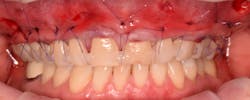

5. A full subperiosteal flap is then tunneled with appropriate instruments, and multiple A-PRF membranes are introduced inside the elevated tissue (figure 13). The gums are advanced toward the CEJ, and a tension-free flap release is performed and stabilized with sutures.

Coronally advanced flap (CAF) is maintained using an apical mattress suture (figure 14). Glycolon sutures 5.0 or 6.0 are the desired sutures to be able to maintain the flap in close contact with root proximity for at least three to four weeks.

This new biological approach involving blood derivatives A-PRF and I-PRF combined with precision minimally invasive surgery for root coverage demonstrates faster healing without the need of a donor site. The morbidity of GDT is decreased and patient case acceptance is higher compared with traditional grafts. Before-and-after pictures are shown below (figures 15–22).